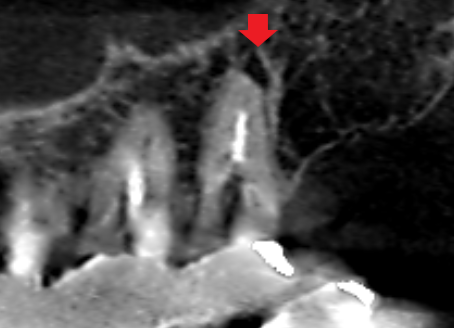

上顎第二大臼歯の口蓋根の矢状断のCT画像です。

矢印の上顎第二大臼歯の口蓋根の先に膿の影がみられます。